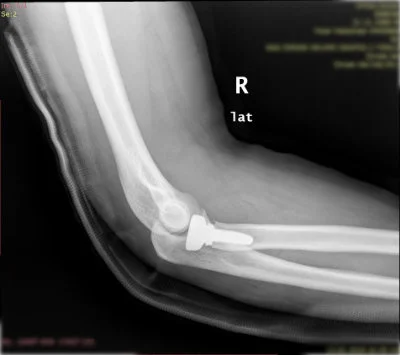

Kas-iskelet sisteminin tüm kırık ve çıkıkları, kas, tendon ve sinir yaralanmaları geniş bir yelpazeyi kapsamaktadır. Her kırık kendi özelinde ayrı ayrı değerlendirilmeli ve her kırık için ameliyat planlaması bu bağlamda yapılmalıdır. Özellikle pelvis-asetabulum kırıkları ortopedik travmada bizler için önemli bir yer tutmaktadır. Bu bölge kırıklarını başarı ile tedavi etmekteyiz.

Özellikle kalça, diz, omurga, kol ve bacak kırıkları gibi durumlarda hızlı ve doğru müdahale, iyileşme sürecini büyük ölçüde etkiler.

Prof. Dr. Halil Burç kliniği olarak, bu tür acil durumlarda sadece yaraları dikmek ya da kırığı sabitlemekle yetinmiyor; hastanın uzun vadeli hareket kabiliyetini, konforunu ve yaşam kalitesini korumayı hedefliyoruz. İleri düzey tekniklerle yapılan ameliyatlar sayesinde, hastalarımızın günlük yaşamlarına en kısa sürede ve en az sakatlıkla dönebilmesi için çalışıyoruz.